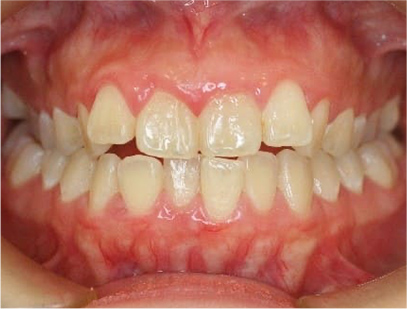

前歯にデコボコがあり、前歯が咬み合っていない症例

上下の前歯が咬んでいない事、上の前歯にデコボコがある事を主訴として来院されました。

通常通りの検査を行い「前歯部にデコボコを伴う開咬」と診断されました。

治療前

• 正面

• 上側

• 右側

• 左側

治療前の写真を比べると上下の前歯は綺麗に並び、歯が出ていたことも改善され、 上下の歯はしっかり咬み合っています。 治療期間は、重度の開咬であったために3年弱を必要としました。